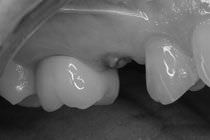

В ходе масштабного исследования японские ученые установили статистически значимую связь между потерей зубов и повышенным риском таких заболеваний как рак пищевода, рак головы и шеи, а также рак легких.

В исследовании, проведенном сотрудниками Университета Нагойи, приняли участие 5240 пациентов с указанными видами онкологических заболеваний, а также 10 480 здоровых добровольцев. По подсчетам ученых, плачевное состояние зубов было связано с увеличением риска рака пищевода на 136 процентов, риска опухолей головы и шеи на 54 процента, а рака легких – на 68 процентов. Вероятность развития всех перечисленных заболеваний возрастала пропорционально числу отсутствующих зубов.

Как подчеркивают авторы исследования, эта закономерность сохранялась после учета таких факторов как потребление алкоголя и курение. С другой стороны, она существенно варьировалась в зависимости от пола и возраста исследуемых. Так, риск развития рака головы и шеи, а также рака пищевода, был более отчетлив у женщин и пациентов моложе 70 лет, и менее выражен у мужчин и пожилых пациентов.

Ученые не исключают, что связанные с потерей зубов хронические воспалительные процессы могут быть одной из непосредственных причин развития злокачественных опухолей. Вполне вероятно также, что отсутствие зубов является одним из признаков нездорового образа жизни. В то же время болезни зубов и десен связаны с существенными ограничениями в пище, что не позволяет пациентам из группы риска компенсировать риск опасных заболеваний за счет здоровой диеты.

В любом случае, подчеркивают авторы исследований, гигиена полости рта и уход за зубами играют ключевую роль в сохранении здоровья человека.